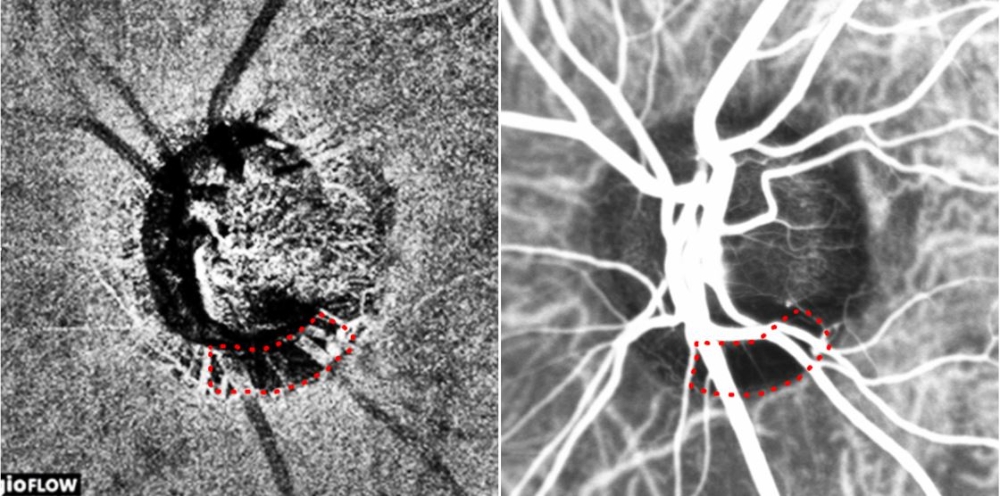

빛간섭단층 혈관조영검사(좌) 및 인도시아닌그린 혈관조영검사(우)로 얻은 녹내장 환자의 시신경유두 이미지. 붉은색 점선으로 둘러싸인 비관류 영역(혈류가 감소한 영역)이 일치한다.

이미지 확대보기연구팀은 시신경 혈류 저하를 보인 녹내장 환자 30명을 대상으로, 기존의 침습적 검사인 인도시아닌그린(특수 형광물질로 조영제의 일종) 혈관조영검사와 빛간섭단층 혈관조영검사를 통해 각각 관찰한 시신경유두 이미지를 비교 분석했고, 그 결과 시신경 주위에 맥락막 혈류가 국소적으로 감소한 영역이 두 검사에서 일치한다는 사실을 발견했다.

이는 녹내장 환자의 시신경 혈류 저하를 관찰하는데 있어 비침습적 검사법이 기존의 침습적 검사 못지않게 정확하다는 의미다.